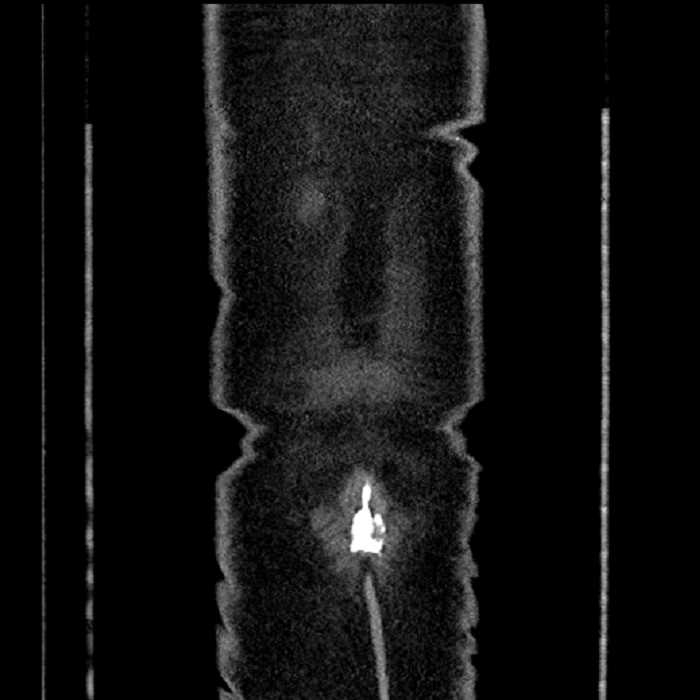

• Mild mural thickening of a segment of the sigmoid colon with adjacent fat stranding and a 1.5 cm fluid and gas collection along the tip of an inflamed diverticulum

• Loss of the normal fat plane between this collection and adjacent loops of small bowel, which demonstrate mural thickening

Acute sigmoid diverticulitis complicated by a small contained perforation and a large abscess in the right hepatic lobe. Additional small subcapsular abscesses along the anterior margin of the left hepatic lobe.

Additionally, loss of the normal fat plane between the peridiverticular collection and adjacent thickened loops of small bowel raises the potential for an enterocolonic fistula.

Hepatic abscess showing the double target sign with low density internally surrounded by a thin inner enhancing rim (red arrow) and ill-defined outer low density rim (yellow arrow). Blue arrow indicates an internal septation. Red arrows: additional smaller subcapsular abscesses. Red arrow: focal contained perforation associated with diverticulitis.